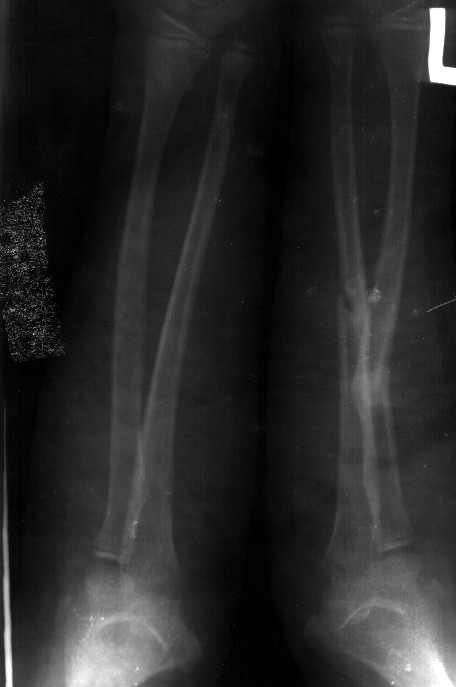

Сделал симметричные снимки с максимальной супинацией и пронацией при согнутом предплечье в 90 град. Объем ротационных движений 90-100 град.

СМ> Сделал симметричные снимки с максимальной супинацией и пронацией при

СМ> согнутом предплечье в 90 град. Объем ротационных движений 90-100 град.

Снимок один сделан с супинацией, второй - оба предплечья в одинаково нейтральном положении. то есть по этим снимкам объем ротационных движений не оценить. Снимко в двух проекциях лучше и делать в среднем положении между пронацией и супинацией, то есть обе проекции в однм и том же положении, когда линия, проходящая через шиловидные отростки, идет в плоскости головки. Прошу прощения за усложнение простых вещей.